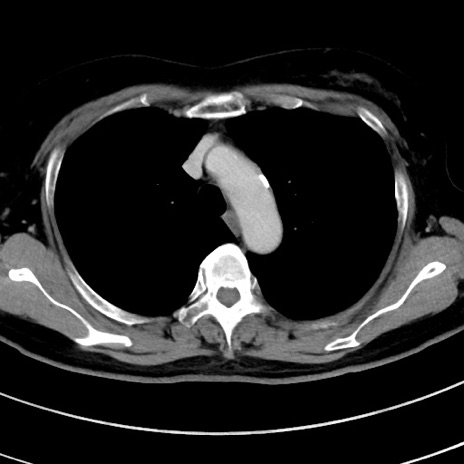

症例9(横断像)

【症例】 60歳代女性

【主訴】むかつき、みぞおちの痛み

【現病歴】3日前よりむかつきがあり、食事がとれない。

【既往歴】糖尿病

【身体所見】発熱なし、心窩部圧痛軽度あるも、腹膜刺激症状なし。

【データ】WBC 7400、CRP 1.92